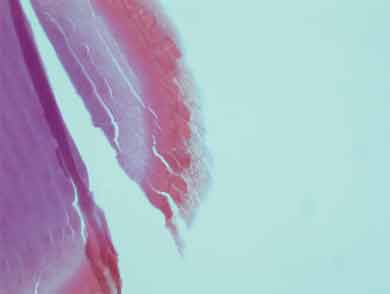

The original foreign body extracted during surgery was compared with a specimen of crayfish antennae and was found to be similar to the very outer layer (1–2 μm) of the specimen (Box 2). It most likely became lodged while the patient was handling crayfish or cleaning the crayfish tank without eye protection, which he was doing extensively during the morning that the red eye developed. The crayfish caught in this area are of several different types, although the Panulirus ornatus (tropical rock lobster) make up 95% of the local population.1